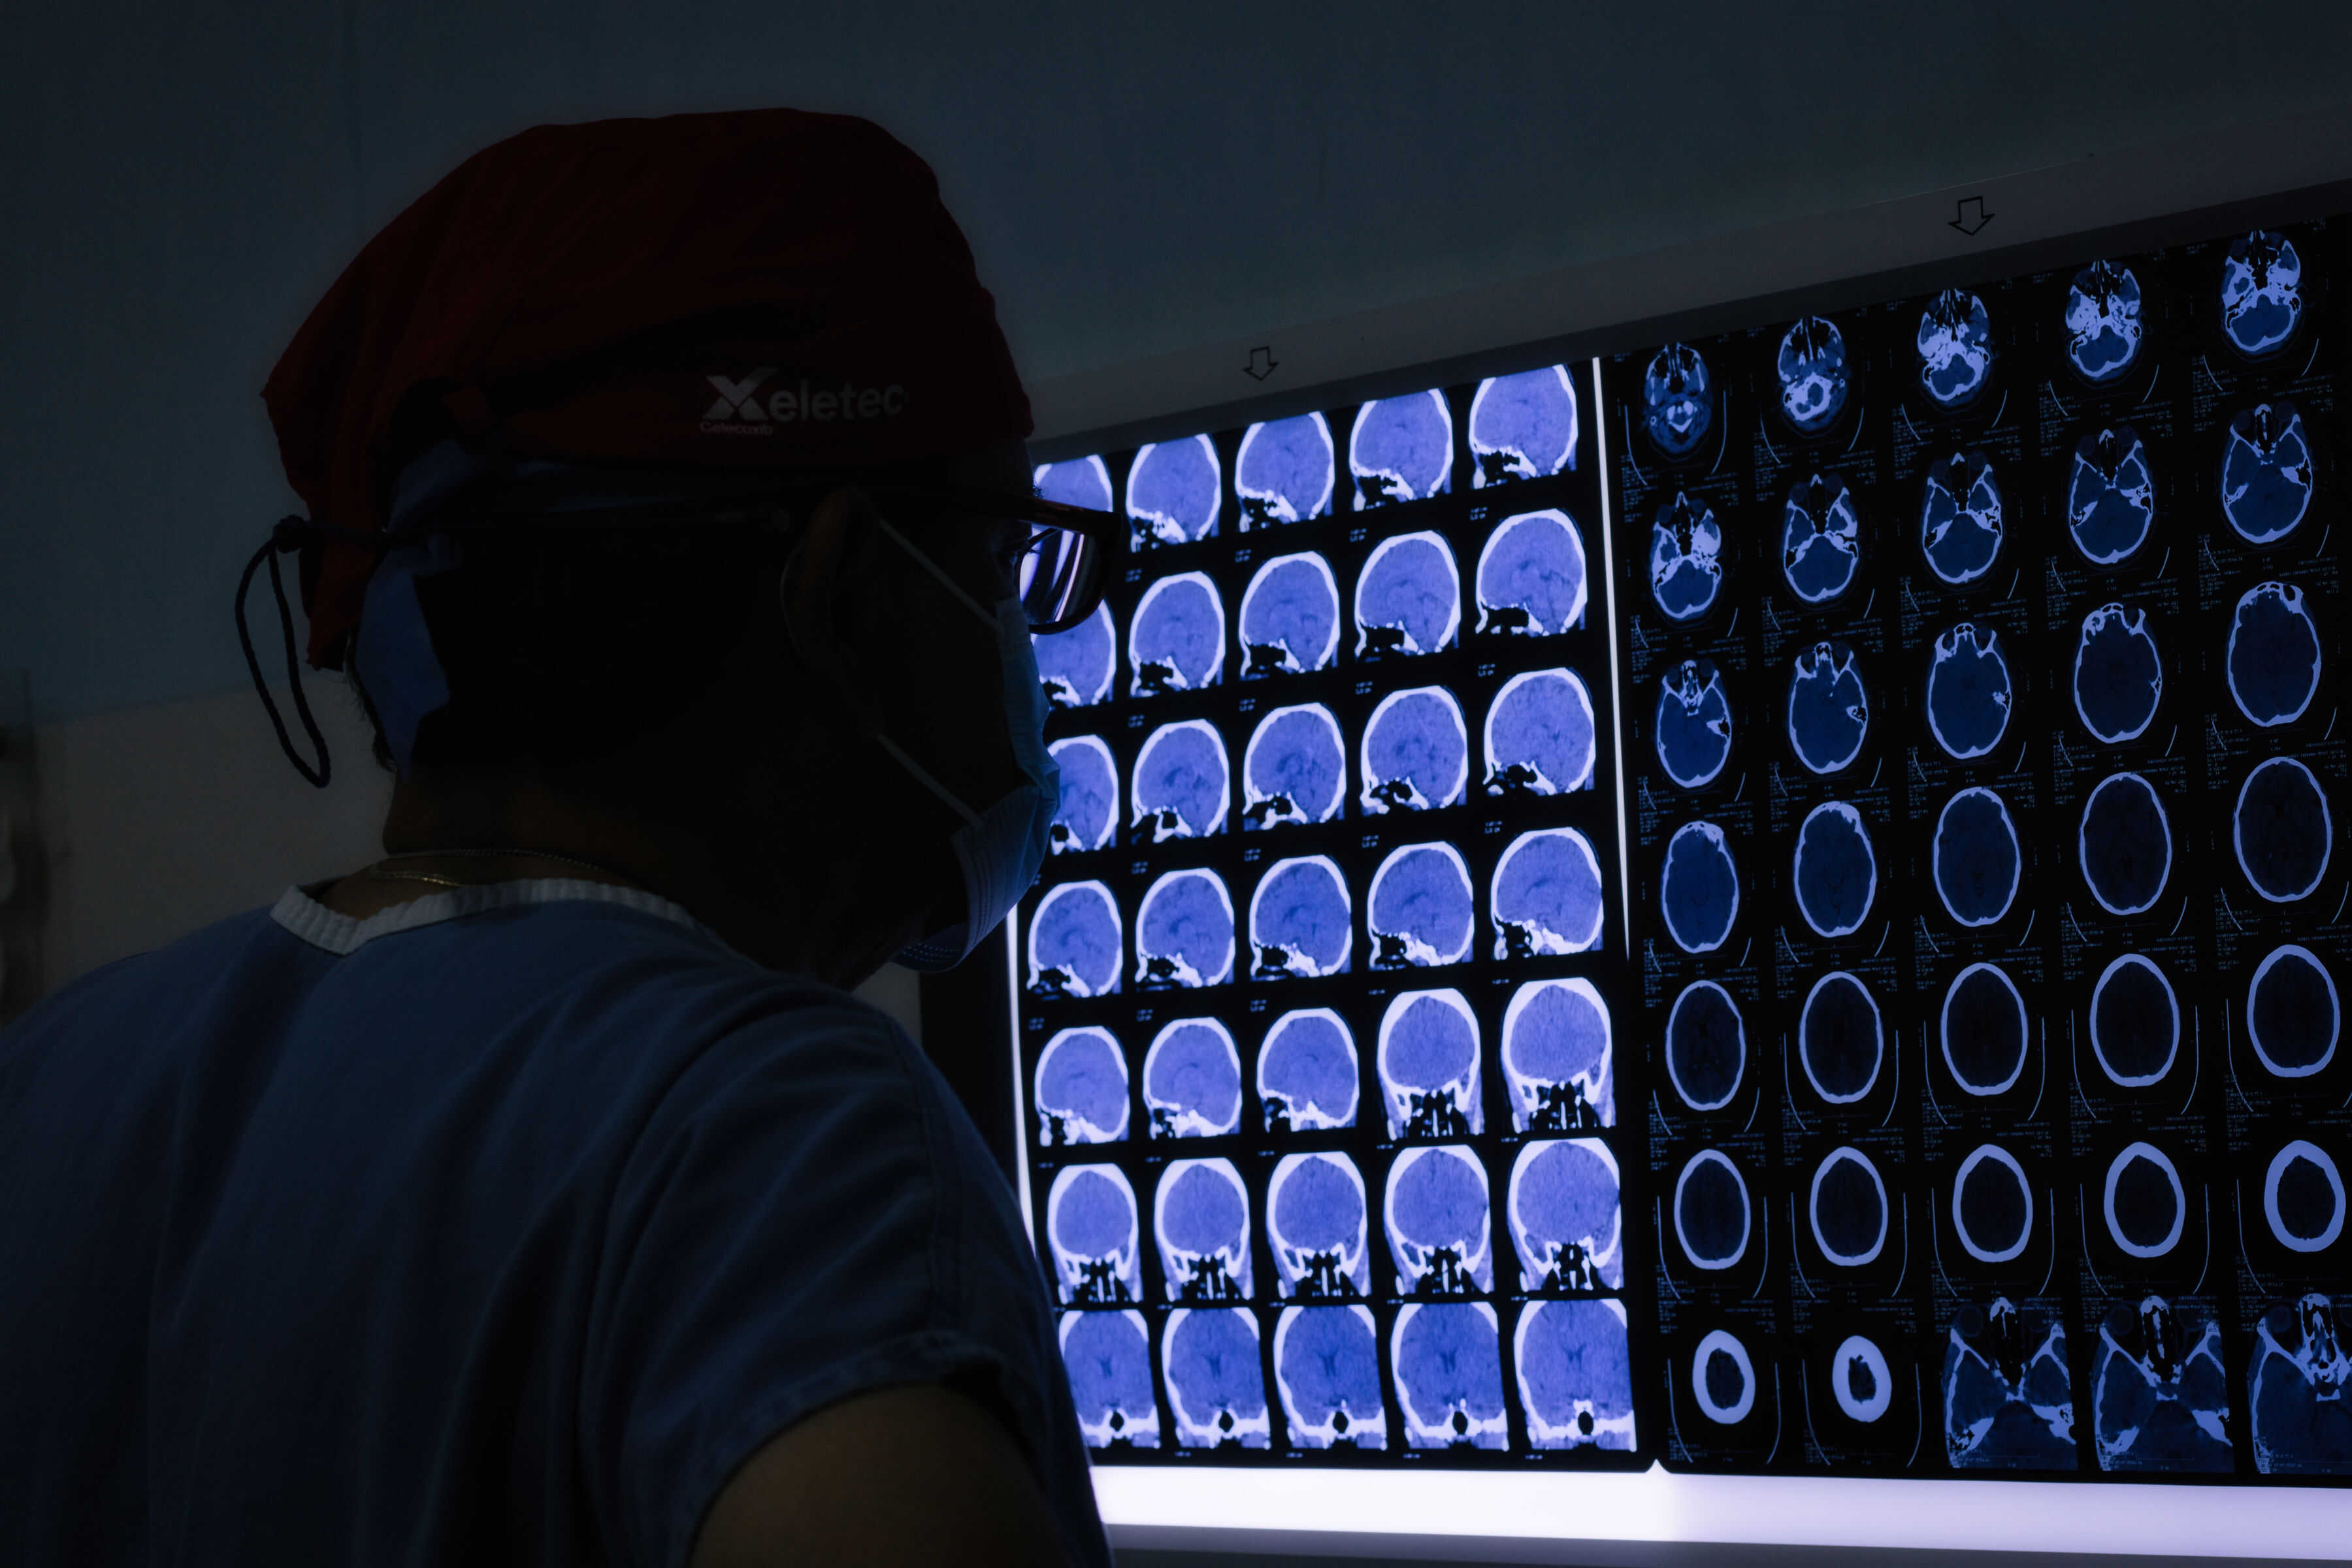

Utilizamos instrumentos de alta tecnología para navegar a través del cerebro y de la columna.

Utilizamos equipos de última generación para realizar diagnósticos precisos y tratamientos innovadores que minimizan el riesgo y aceleran la recuperación. Esta fusión entre experiencia y tecnología permite ofrecerle procedimientos altamente efectivos, con menor dolor postoperatorio, estancias hospitalarias reducidas y un retorno más rápido a su calidad de vida habitual. Su salud está en manos expertas que priorizan siempre la seguridad y el bienestar del paciente.